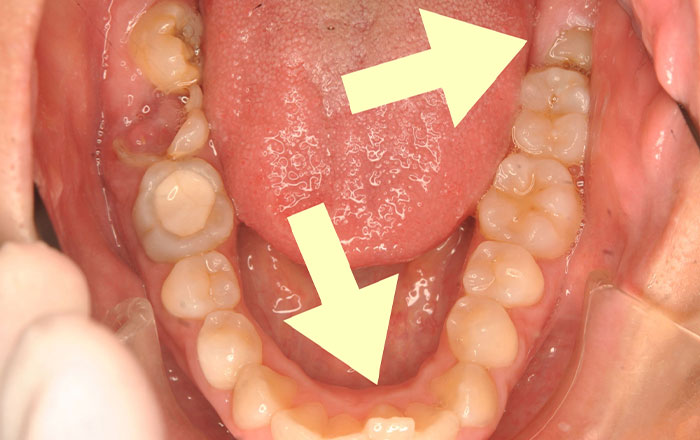

・親知らずが横に傾いて、隣の歯に被るように生えている

・親知らずが半分しか生えていないという生え方をしている場合、抜歯をおすすめしています。

親知らずが半分だけ生えているなど状態とは、しっかり生えておらず、歯ぐきに隠れて半分だけ歯が出ている状態です。

完全に生え図に、隣の歯に比べて高さが低いという歯もあります。

歯が半分だけ生えるのは、顎が骨格が小さく、まっすぐ生えるスペースがなく、隣の歯に引っかかって生えてこないことが多いためです。

親知らずが半分だけしか生えていない場合は、隣の歯と段差もあり、親知らずの箇所の歯みがきが難しく、バイ菌が残りやすくなってしまいます。

歯ぐきが上に覆いかぶさった状態だと、歯ぐきと親知らずの間にバイ菌が溜まり、腫れと痛みを何回も繰り返すこともあります。